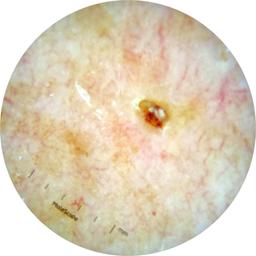

ISIC_7193897

IP_3751325

IL_3780211

Clinical

Field Value

acquisition_day 251

age_approx 65

anatom_site_1 Lower extremity

anatom_site_general lower extremity

concomitant_biopsy False

diagnosis_1 Benign

diagnosis_confirm_type single image expert consensus

family_hx_mm False

image_manipulation instrument only

image_type dermoscopic

lesion_id IL_3780211

patient_id IP_3751325

personal_hx_mm True

sex female